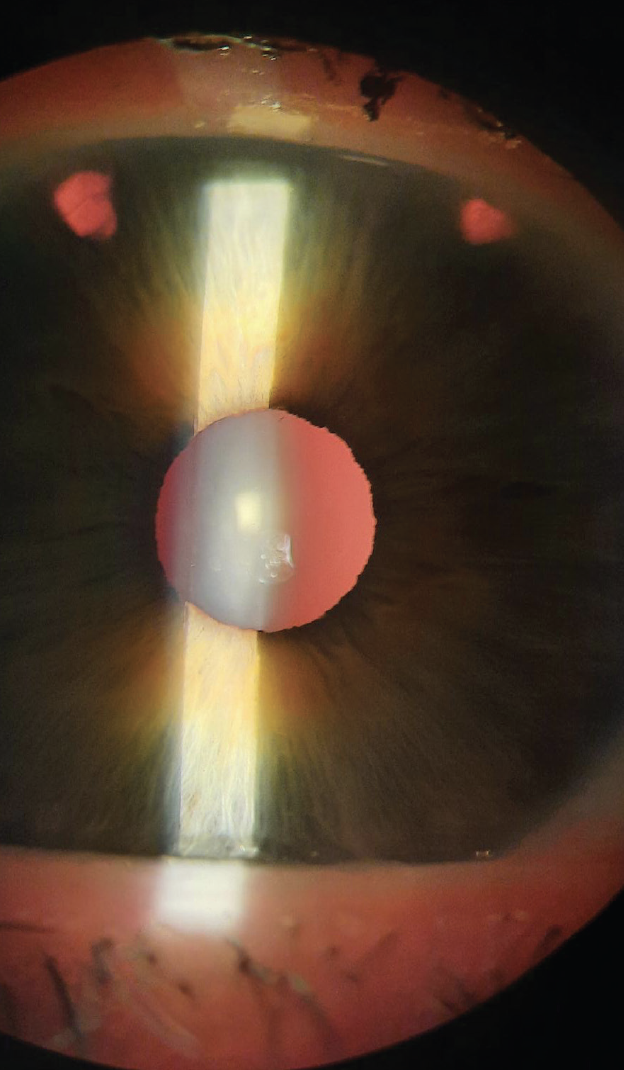

The Visian ICL (STAAR Surgical) is currently the most widely used phakic IOL in the United States. A toric version of this lens (Visian Toric ICL, STAAR Surgical) was approved in 2018 (Figure 1). A second phakic IOL available in this country is the Verisyse IOL (Johnson & Johnson Vision in the United States; available elsewhere as the Artisan lens from Ophtec). The Verisyse is less popular than the Visian ICL in the United States because of differences in design; the former is a rigid PMMA lens that requires a large incision for implantation, whereas the Visian ICL is a foldable lens that requires a small incision.

Figure 1. A Visian ICL placed in the ciliary sulcus.

Figure courtesy of STAAR Surgical.